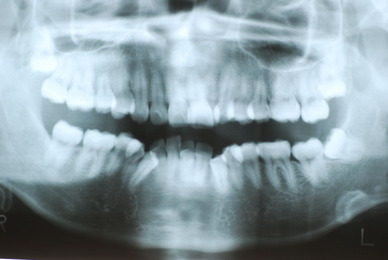

今回の方は、何十年にもわたりやすい保険の入れ歯で苦労したのです。それで自分で修理しながら使用していたという猛者でした。

所が、見た目も悪くこれでどうやって人と会っていたのか、食べていたのか皆目想像できない方でした。

カビか何かが入り込んでいる異様な入れ歯でした。

上の歯は一本がブラブラでしたね。

下顎が右にシフトしているので噛み合わせはとても慎重にしました。下の方が頬側にないと安定せず噛めないのです。